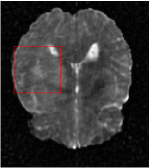

All the experiments are implemented on a Windows workstation with Intel Core i9 CPU at 3.3GHz and an Nvidia GTX-1080Ti GPU with 11GB of graphics card memory via TensorFlow Abadi et al. (2016). The parameters in the proposed network are initialized by using Xavier initialization Glorot and Bengio (2010). We trained the meta-learning network with four tasks synergistically associated with four different CS ratios: 10%, 20%, 30%, and 40%, and test the well-trained model on the testing dataset with the same masks of these four ratios. We have 300 training data for each CS ratio, which amount to total of 1200 images in the training dataset. The results for and MR reconstructions are shown in Tables 5.4 and 5.4 respectively. The associated reconstructed images are displayed in Figures 1 and 3. We also test the well-trained meta-learning model on unseen tasks with radio masks for skewed ratios: 15%, 25%, 35%, and random Cartesian masks with ratios 10%, 20%, 30% and 40%. The task-specific parameter for the unseen tasks are retrained for different masks with different sampling ratios individually with fixed task-invariant parameters . In this experiments, we only need to learn for three skewed CS ratios with radio mask and four regular CS ratios with Cartesian masks. The experimental training proceed on less data and iterations, where we performed on 100 MR images with 50 epochs. For example, for reconstructing MR images with CS ratio 15% radio mask, we fix the parameter and retrain the task-specific parameter on 100 raw data with 50 epochs, then test with renewed on our testing data set with raw measurement that sampled from radio mask with CS ratio 15%. The results associated with radio masks are shown in Table 5.4 and 5.4, Figure 2 and 4 for and images respectively. The results associated with Cartesian masks are list in Table 5.4 and reconstructed images are displayed in Figure 5.

Qualitative comparison between conventional and Meta-learning methods are shown in Figure 1 and 3, which display the reconstructed MR images of the same slice for T1 and T2 respectively, we label the zoomed-in details of HGG in the red boxes. We observe the evidence that conventional learning is more blurry and lost sharp edges, especially in lower CS ratios. From the point-wise error map, we find meta-learning has the ability to reduce noises especially in some detailed and complicated regions comparing to conventional learning.